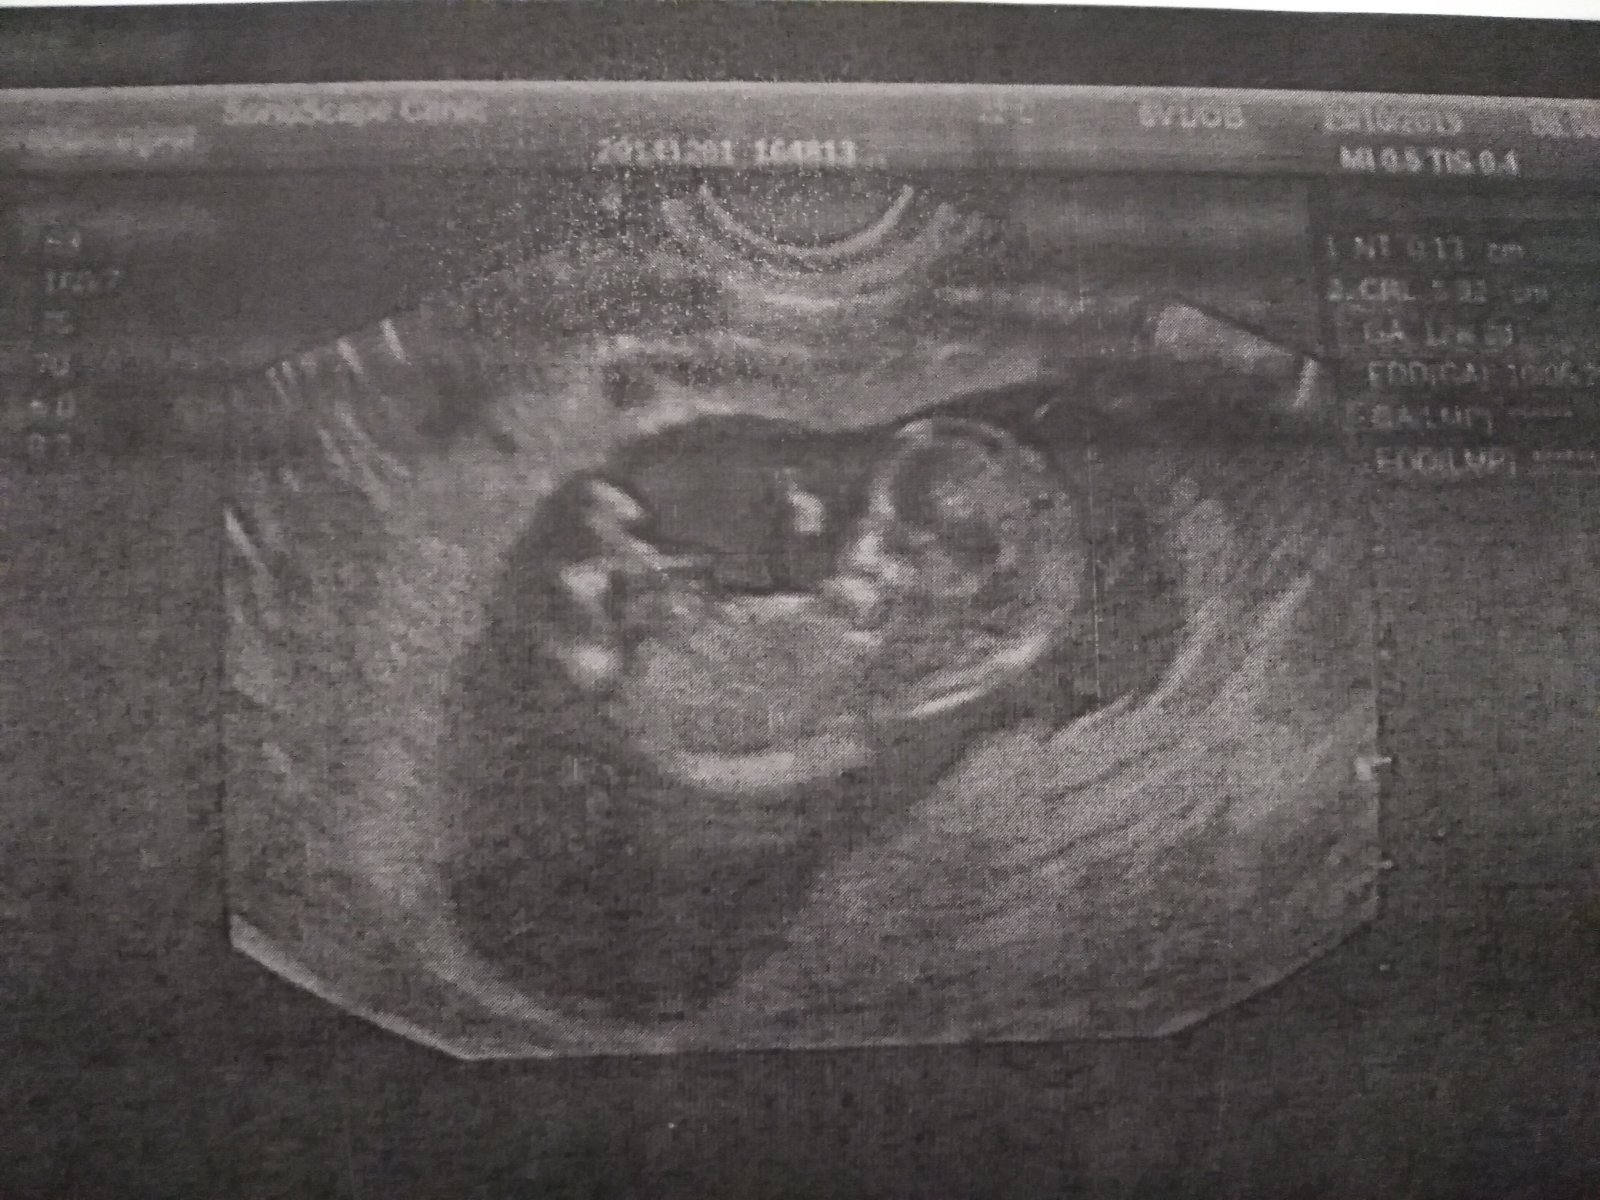

Ahoj holky, ja dnes ultrazvuk a bilo i srdicko ❤️

Za tyden jdu zas

Ahoj holky, tak dalsi kontrola zamnou a vse v poradku 😍